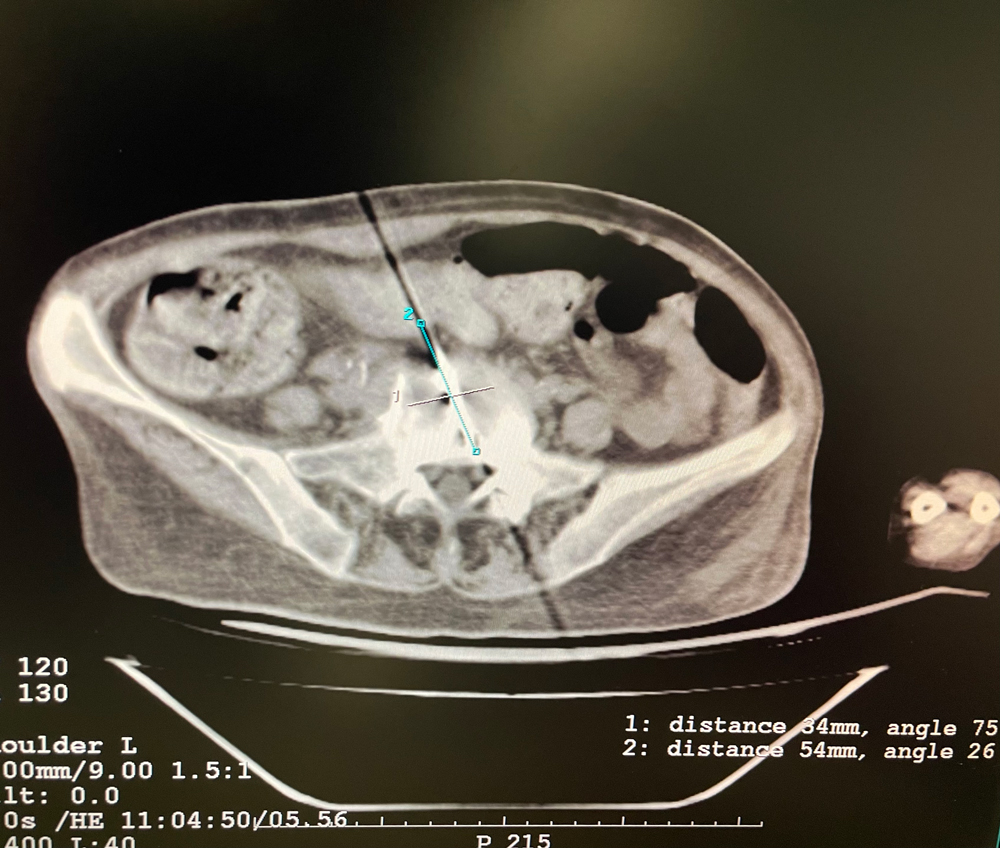

女,56歲,肺轉移瘤,骶骨、左側肋骨各一轉移灶,病灶大小均為5cm。骶骨轉移灶、肋骨轉移灶各進(jìn)行2個(gè)凍融循環(huán)。患者術(shù)后狀況良好。